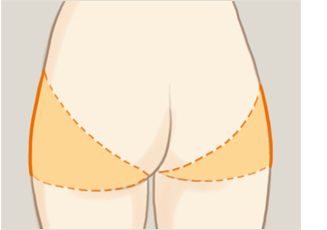

假体隆胸整形手术主要是将假体植入到胸部的部位,使得胸部变得浑圆饱满起来,从而达到了隆胸整形的目的。